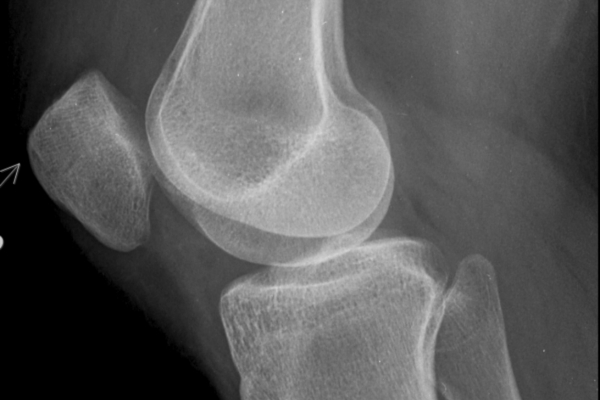

Usually, the phrase refers to reduced joint space seen on an X-ray.

That means the cushioning cartilage between the bones has worn down significantly in part of the joint.

But an X-ray is only one piece of the story.

It shows structure — not function.

That means two people can have similar X-rays and very different symptoms.

One person may struggle to walk.

Another may still golf, travel, and function fairly well.